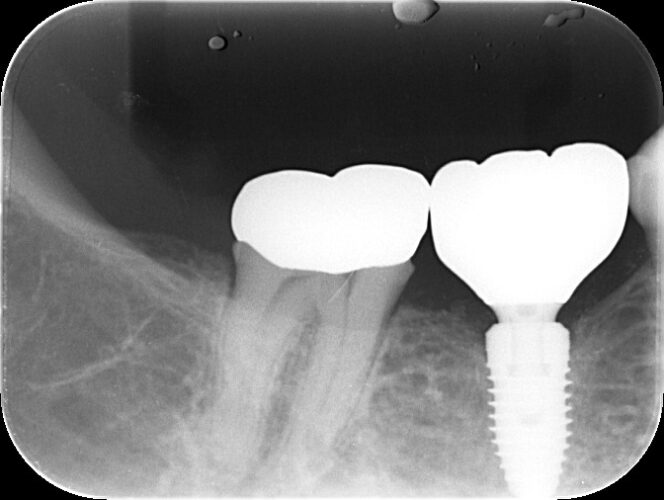

この患者様は2021年3月に右下にインプラントを埋入し、3ヶ月間オッセオインテグレーション(骨とチタンの結合)を待ち、最終的にジルコニアでできた被せ物を装着しました。

こちらがジルコニアでできた被せ物を装着後のレントゲン写真です。